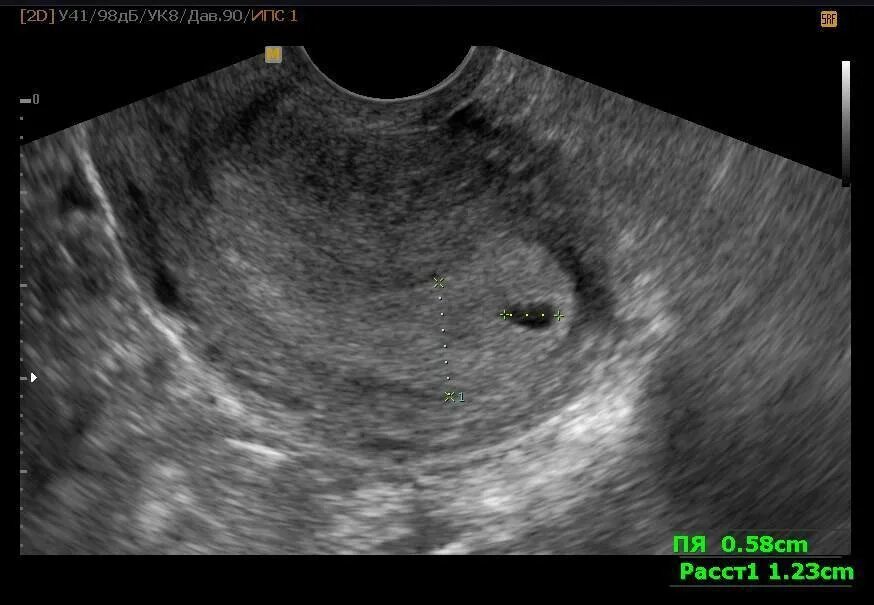

Эмбрион не прикрепился к матке причины